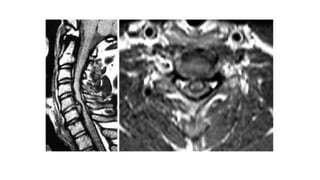

DIAGNOSTICO

RX RM

TOMOGRAFIA

ESTENOSIS CERVICAL

-Estrechez del conducto que contiene

la médula espinal, las raíces nerviosas y los

vasos a nivel del segmento vertebral C1-C7.